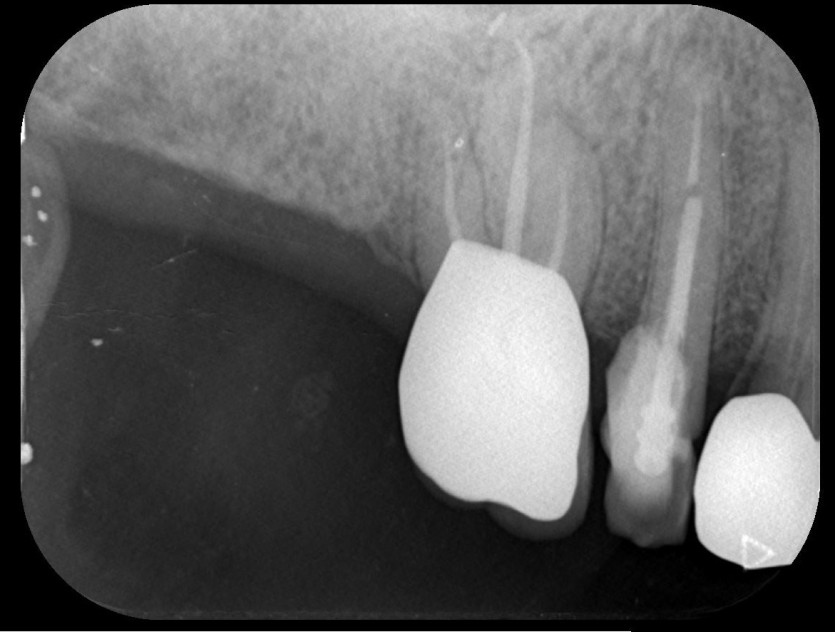

신경치료 사례